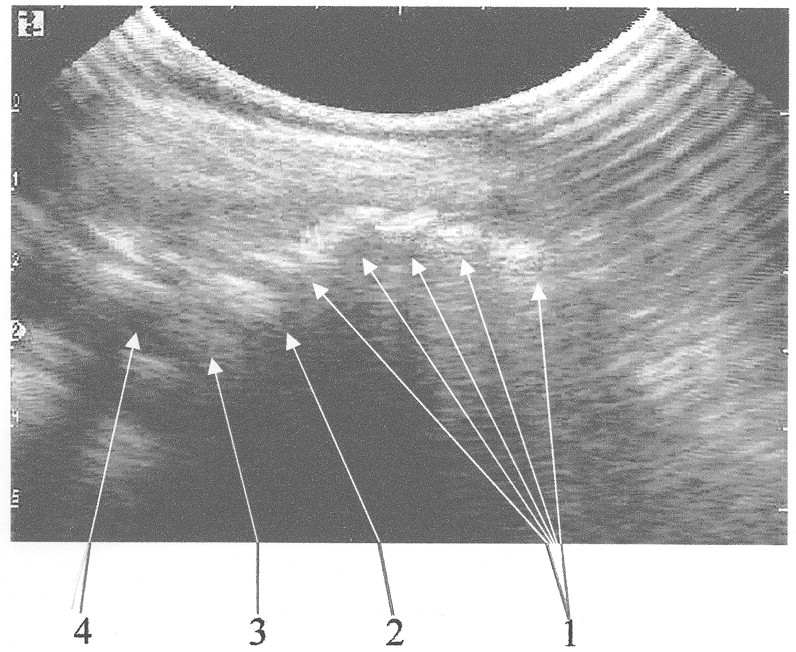

На чертеже представлена сонограмма крестцово-копчиковоо сегмента, получаемая при использовании ультразвукового обследования.

Ребенка укладывают на правый бок. Ноги сгибают в коленях и приводят к передней брюшной стенке. Датчик ультразвукового аппарата помещают в межягодичной складке в проекции крестца перпендикулярно коже в сагиттальной плоскости. Сканирование проводится на частоте 5 MHz, которая обеспечивает достаточную глубину проникновения ультразвуковых волн для визуализации костно-хрящевых структур дистального отдела позвоночника. Датчик постепенно перемещают в каудальном направлении, сохраняя его пространственную ориентацию. Перемещение датчика останавливают, когда на экране визуализируются структуры конечного отдела позвоночного столба: все копчиковые позвонки, представляющие собой на сонограмме гиперэхогенные зоны 1, последний крестцовый позвонок, представляющий собой гиперэхогенную зону большего размера 2, который отделяется от места окончания спинно-мозгового канала соединительнотканной прослойкой 3, которая выглядит как эхоположительная зона меньшей интенсивности, чем от последнего крестцового позвонка, спинно-мозговой канал 4, характеризующийся гипоэхогенной зоной и место его окончания. После этого считают количество копчиковых позвонков на сонограмме, которое имеется у больного, и во время операции после выделения последнего копчикового позвонка отсчитывают в краниальном направлении то число позвонков, которое получено на сонограмме, и прибавляют еще один, которым является последний крестцовый позвонок. Место резекции крестцово-копчикового сегмента должно проходить на границе между соединительнотканной прослойкой, отделяющей место окончания спинно-мозгового канала от последнего крестцового позвонка, и последним крестцовым позвонком, это соответствует краниальному (верхнему) краю последнего крестцового позвонка, что исключает вскрытие просвета спинно-мозгового канала.